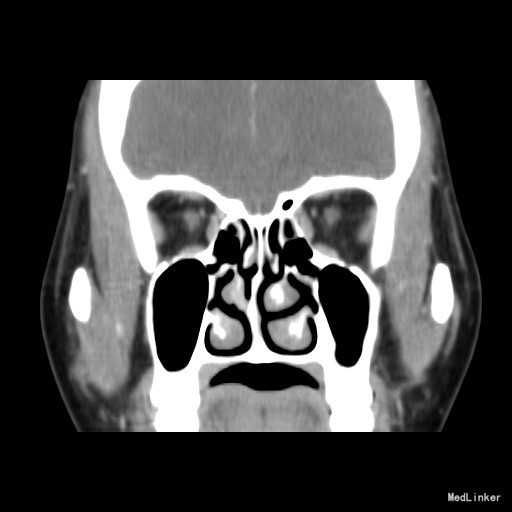

诊断:鼻腔血管瘤 治疗:入院后鼻窦CT示:右侧中鼻甲血管瘤,排除手术禁忌症,于局麻+表麻下手术,术后病理提示:(右侧鼻腔血管瘤)结合临床,可符合血管瘤。